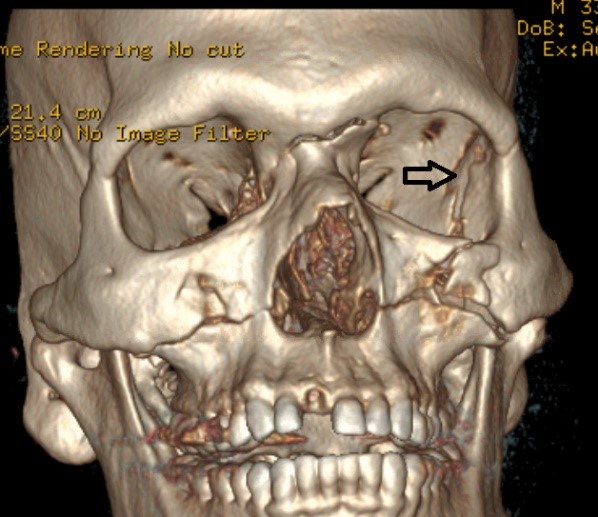

- Accurately identify fractures using CT and 3DCT radiographic findings to prescribe the appropriate treatment required for midface and zygoma fractures.